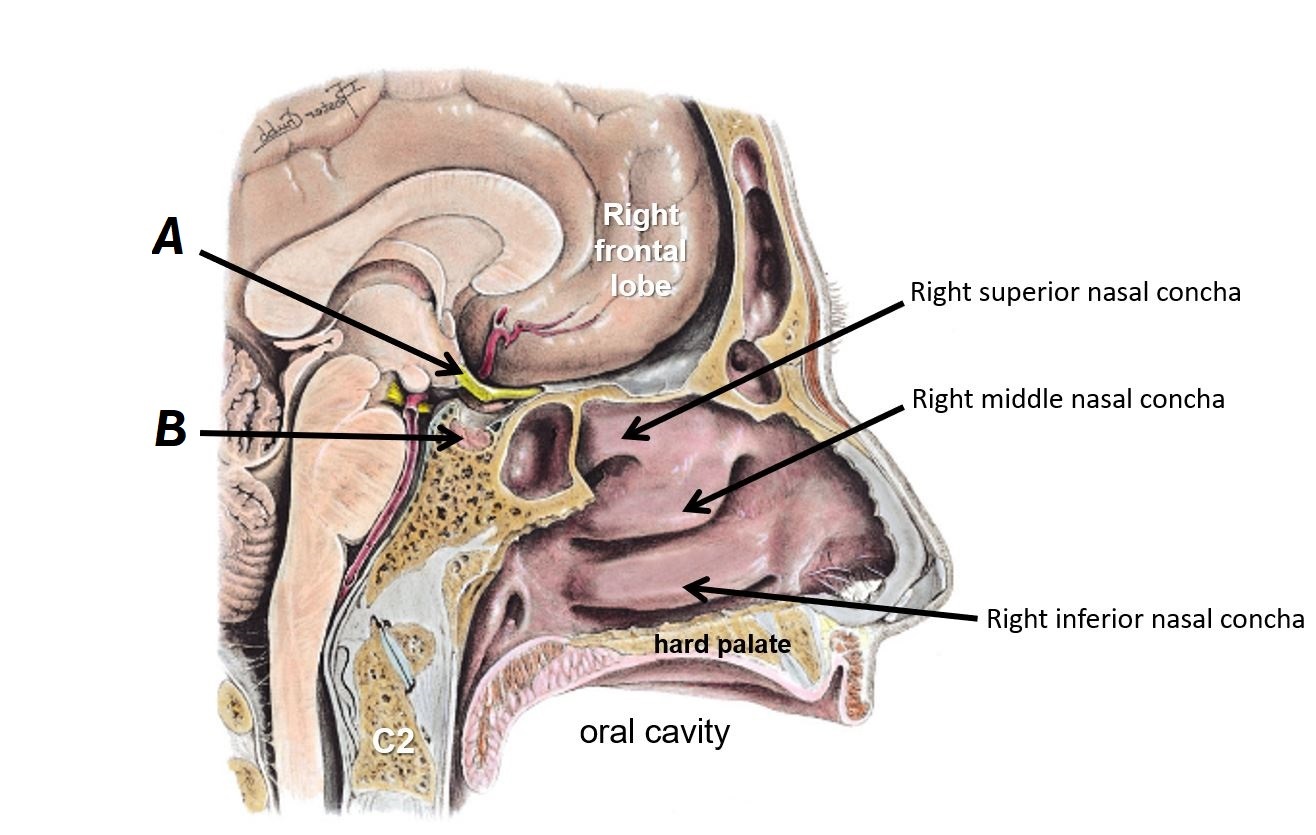

Name structures A and B

A - Optic chiasm

B - Pituitary gland

Name bones A, B and C

A - Superior nasal concha

B - Middle nasal concha

C - Inferior nasal concha